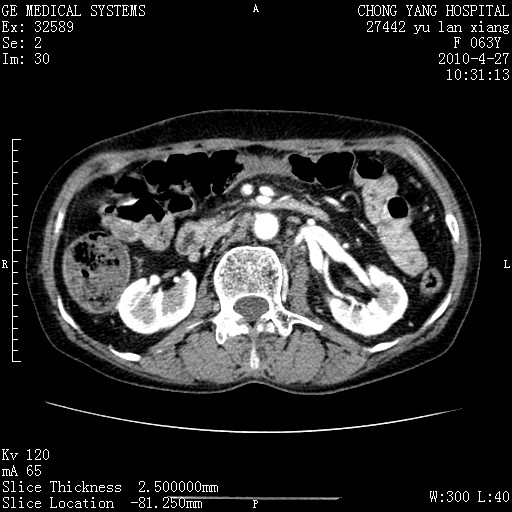

标题: CT26066:F63Y 上腹正中压痛半月,CA199:7400u/ml,MR示胰腺炎伴 [打印本页]

胰腺癌侵犯腹腔动脉干-分支、胃壁、左侧膈肌伴胰周及腹膜后淋巴结转移、胆囊切除术后。

胰腺癌侵犯腹腔动脉干-分支、胃壁、左侧膈肌伴胰周及腹膜后淋巴结转移、胆囊未显影。